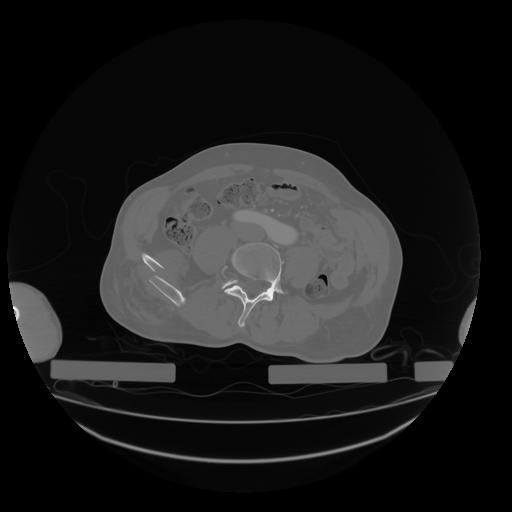

28 CUERPO,CE,Vol,2.0,CUERPO,,